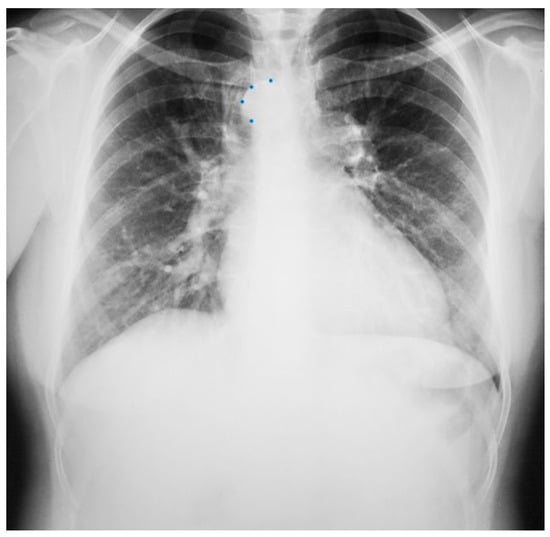

Figure 19.

Posteroanterior chest X-ray of severe pulmonary stenosis: this chest X-ray is of a 31-year-old female who presented with worsening exertional dyspnea over the last two years. Her exam revealed elevated jugular venous pressure with prominent A wave. She was noted to have a right ventricular lift with a grade 4/6 systolic ejection murmur best heard at the left upper sternal border. The chest X-ray is well centered and there is a good inspiration. The cardiothoracic ratio is normal. The pulmonary trunk is enlarged (its right border is outlined by blue dots as it passes over the left bronchus). The left pulmonary artery branch that is indicated by two red arrows is also enlarged. Her echocardiogram revealed severe pulmonary valve stenosis with peak gradient 68 mmHg and mild pulmonary valve regurgitation. She subsequently underwent balloon valvuloplasty with reduction of her peak gradient to 24 mmHg. Her symptoms of dyspnea had resolved a few months post-procedure.